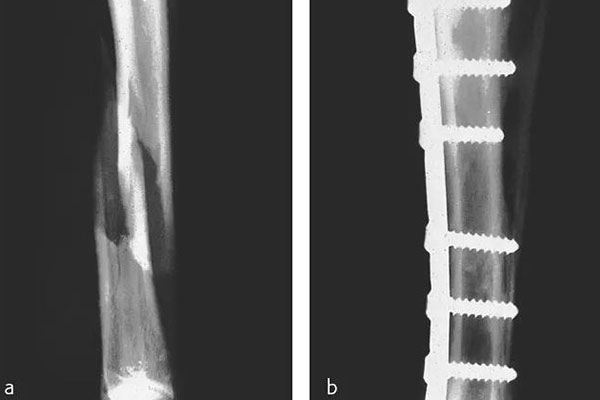

那在檢測(cè)的時(shí)候還需要看到植入物的情況,但由CFPEEK復(fù)合材料制成的零件通常具有放射透性,幾乎無(wú)法通過(guò)X射線檢測(cè)。就通過(guò)添加諸如鉭絲之類的X射線散射材料,可以使植入物變得可見(jiàn)。可以看下圖展示了一個(gè)固定骨折骨頭的骨愈合板。可以看出,通過(guò)設(shè)計(jì)已對(duì)放射密度進(jìn)行了定制,以便在盡量減少對(duì)骨折部位遮擋的同時(shí)可視化組件。重要的是,實(shí)現(xiàn)X射線可見(jiàn)性的同時(shí)也能保持清晰的MRI圖像。